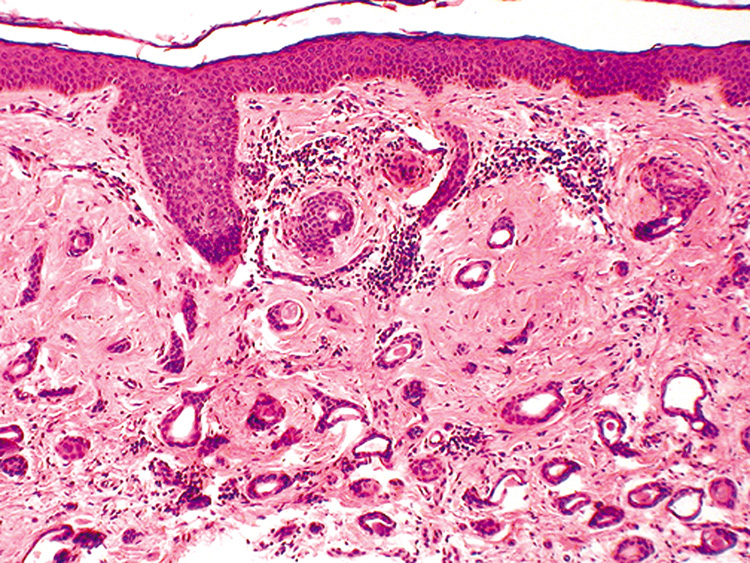

Dermoid Cysts Dermoid cysts are usually present at birth and commonly occur around the eyes. They may be adherent to the periosteum. Dermoid cysts are believed to result from sequestration of skin and its appendages along embryonic lines of closure and, thus, are commonly found at the frontozygomatic suture. Histologically, dermoid cysts are lined by epidermis possessing various mature appendageal structures (Fig. 22). These include hair follicles with terminal hairs, sebaceous glands, eccrine glands, and, occasionally, apocrine glands. Steatocystoma Steatocystoma may occur as solitary cysts (simplex) or multiple cysts (multiplex). The latter is often inherited as an autosomal dominant trait. These cysts are small and firm and, when punctured, exude an oily or creamy fluid. Steatocystoma is derived from cystic dilatation of the sebaceous duct, which empties into the hair follicle. Histologically, the cyst wall is folded and shows several layers of epithelial cells with a palisading of the peripheral cell layer. The cells lining the cystic cavity are covered by a thick, eosinophilic cuticle. Characteristically, flattened sebaceous lobules are present either within or close to the cyst wall. Pilomatrixoma Pilomatrixoma, also referred to as Malherbe's calcifying epithelioma, is a cyst derived from the hair matrix that forms the hair. It is often a solitary lesion and most commonly occurs on the face. Most pilomatrixomas occur in the first two decades of life and, if superficially located, produce a blue-red skin discoloration. Excision is curative. Histologically, pilomatrixomas show two types of cells in variable proportions: a basophilic cell with a dark basophilic nucleus and scanty cytoplasm and a “shadow cell,“ which has an unstained central nucleus and faintly eosinophilic cytoplasm (Fig. 23). There may be an abrupt or gradual transition between the two cells, and few or no basophilic cells may be seen in “old“ lesions. Calcification of pilomatrixoma is frequent and may occur within the shadow cells or in the stroma. The stroma usually is fibrotic and contains a foreign body reaction. Ossification also can occur occasionally. “Hybrid“ Cysts Follicular cysts with differentiation toward two or more of the previously mentioned cysts are referred to as hybrid cysts. Although originally described as a cyst of infundibular and trichilemmal keratinization, hybrid cysts may show any permutation of follicular keratinization. BENIGN TUMORS Epithelial Derivation FIBROEPITHELIAL PAPILLOMA (ACROCHORDON) The fibroepithelial papilloma, also known as a squamous papilloma, acrochordon or skin tag, is a polyp of skin that occurs commonly on or around the eyelids. Histologically, fingerlike projections of papillary dermis are covered by epidermis, which is of normal thickness and shows elongation of the rete ridges and hyperkeratosis. Dilated capillaries are seen in the dermis with a variable chronic inflammatory infiltrate (Fig. 24). If traumatized, there may be necrosis of the epidermis and dermis with ulceration and crust. SEBORRHEIC KERATOSIS. Seborrheic keratoses are the most common benign skin lesions in the geriatric population. They typically increase in size and number with age. Clinically, the lesions are well-demarcated, tan-to-brown papules or plaques with a rough, almost warty, “stuck on“ appearance. Due to their pigmentation, distinguishing the lesions from malignant melanoma is sometimes difficult. In some cases, seborrheic keratoses may be polypoid, resembling papillomas, or shiny and glistening, resembling basal cell carcinomas. Although clinically confused with both melanoma and basal cell carcinoma, they are not thought to be a precursor to malignancy. Histologically, seborrheic keratoses are composed of a proliferation of basaloid cells resembling the basal cell layer of the epidermis (Fig. 25). Six subtypes are recognized: acanthotic, hyperkeratotic, reticulated, clonal, irritated, and melanoacanthoma. All types show acanthosis, hyperkeratosis, and papillomatosis. Because the acanthosis produces an upward extension, the lower border of seborrheic keratoses is even, and a straight line can be drawn from one end of the tumor to the other. A characteristic feature of seborrheic keratoses are the horn pseudocysts, which are horny invaginations cut on cross section. Dermatosis papulosa nigra is a small, pigmented, polypoid seborrheic keratosis seen around the eyes and on the cheeks of Black people. The sudden appearance of numerous seborrheic keratoses, called the Leser-Trélat sign, may herald an internal malignancy. EPIDERMAL NEVUS. Epidermal nevi (nevus verrucosus) are linear verrucous plaques usually present at birth. The lesions may be localized or, rarely, generalized. The latter type may be associated with skeletal or central nervous system abnormalities (epidermal nevus syndrome). There are two major classifications of epidermal nevi: nonorganoid (keratinocytic) and organoid (sebaceous, follicular, and sweat gland). The type of epidermal nevus is determined by its predominant components, keratinocytes, or epidermal appendages. Histologically, there is considerable hyperkeratosis, papillomatosis, and acanthosis with fusion of the rete ridges. Epidermolytic hyperkeratosis may be seen in the localized or, more frequently, the generalized type. INVERTED FOLLICULAR KERATOSIS. Inverted follicular keratosis is a benign epithelial lesion occurring exclusively on hair-bearing surfaces and, most frequently, the face. Middle-aged or older individuals are usually affected. Clinically, the lesion presents as an asymptomatic, pink or flesh-colored papule or plaque. Rapidly growing lesions may be confused with keratoacanthomas. Histologically, inverted follicular keratoses are exoendophytic and symmetric. There is a bulbous proliferation of keratinocytes showing abundant eosinophilic cytoplasms into the dermis. Often, the stratum corneum is parakeratotic and contains neutrophils, serum, and red blood cells. A characteristic feature, which is also shared with irritated seborrheic keratoses, is the presence of squamous eddies, which are whorls of eosinophilic keratinocytes arranged in an onion-peel fashion (Fig. 26). Some authors believe that inverted follicular keratoses are really irritated seborrheic keratoses or verrucae with squamous eddies. WARTY DYSKERATOMA Warty dyskeratoma presents as an umbilicated keratotic papule resembling a keratoacanthoma, but can also be confused with a squamous cell carcinoma. It occurs primarily on the scalp, face, or neck. The characteristic histologic features are a cupshaped invagination filled with keratinous material and acantholytic, dyskeratotic cells. Villi of dermal papillae project into the base of the crater and are lined by a single layer of basal cells. Corps ronds, which are dyskeratotic cells containing a pyknotic nucleus surrounded by a clear halo, are seen in the granular layer at the entrance of the invagination (Fig. 27). The presence of acantholytic dyskeratosis with corps ronds is reminiscent of Darier's disease, but warty dyskeratoma is believed to represent a distinct cutaneous tumor with histologic resemblance to Darier's disease. Melanocytic Derivation MELANOCYTIC NEVUS. Nevi can be classified as ordinary nevi, spindle-cell nevi (Spitz), blue nevi, cellular blue nevi, plexiform spindle-cell nevi, or a combination of any of the above based on cell type and location (Fig. 28). Melanocytic nevi first appear as small, tan, flat macules around 6–12 months of age; they enlarge radially with body growth, and regress in later life. Clinically, they are distinguished from melanoma by their characteristic homogenous pigmentation, symmetric and well-defined borders, and smaller diameter (<5 mm). Pertaining to the periocular region, kissing nevi are congenital nevi that appear symmetrically on adjacent aspects of the upper and lower eyelids and are formed secondary to melanocytic migration to this aspect of the lids prior to separation of the embryonic eyelids. Histologically, nevi are composed of benign melanocytes with little pleomorphism or cellular atypia. The overall distribution of melanocytes is symmetrical and they tend to form nests. Melanocytes become smaller with less cytoplasm as they descend deeper into the dermis. Acquired melanocytic nevi can be classified histologically as junctional nevi (cells at dermoepidermal junction), intradermal nevi (cells found only in dermis, not at junction), and compound nevi (combined features of junctional and intradermal nevi) (Fig. 29). Increased risk of malignant transformation occurs as nests of nevus cells migrate from the epidermal to dermal region; thus, junctional and compound nevi more commonly have malignant transformation.